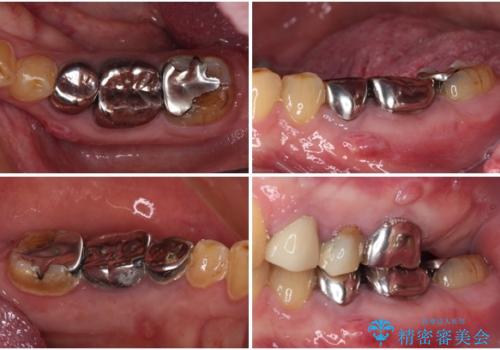

- 上下の奥歯が痛いとのことで来院された患者様です。

診察をしたところ、上下大臼歯の歯肉に排膿路認められたため、根管治療を行い、その後補綴治療を行うこととしました。

また、上顎の欠損部位にはインプラント治療を行うこととしました。